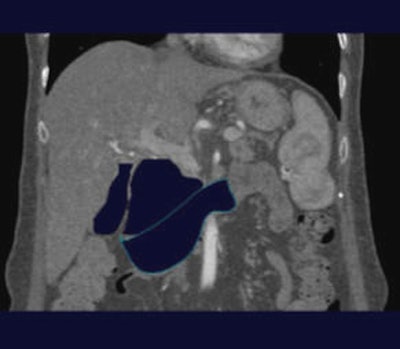

The virtual Whipple begins by manually tracing along the borders of the gallbladder, pancreas and duodenum (images below) using multiplanar reformats to avoid essential anatomy before executing a simple remove algorithm. Subsequently a 3D angiogram can be generated in which arteries which cross through the anticipated surgical planes are color-coded, and thus highlighted to the surgeon.

For planning via the virtual Whipple, arterial-phase MDCT images are sent to an offline workstation (Vitrea 2, Vital Images, Minnetonka, MN). After the algorithm identifies and manually traces the margins of the gallbladder, the organ is isolated and electronically removed from the dataset. Next, the dissection margins of the duodenum and pancreas are drawn, with care to avoid the surrounding vascular structures.

| The margins of the gallbladder, here outlined by positive oral contrast post ERCP, are manually traced. All images courtesy of Dr. Darren Brennan. |

| The gallbladder is then removed by executing a simple remove algorithm. |